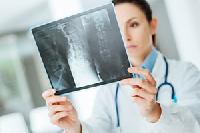

Изучение проблемы низкого качества рентгенограмм на Вашем оборудовании.

Магнитно-резонансная томография (МРТ):один из самых эффективных методов диагностики заболеваний